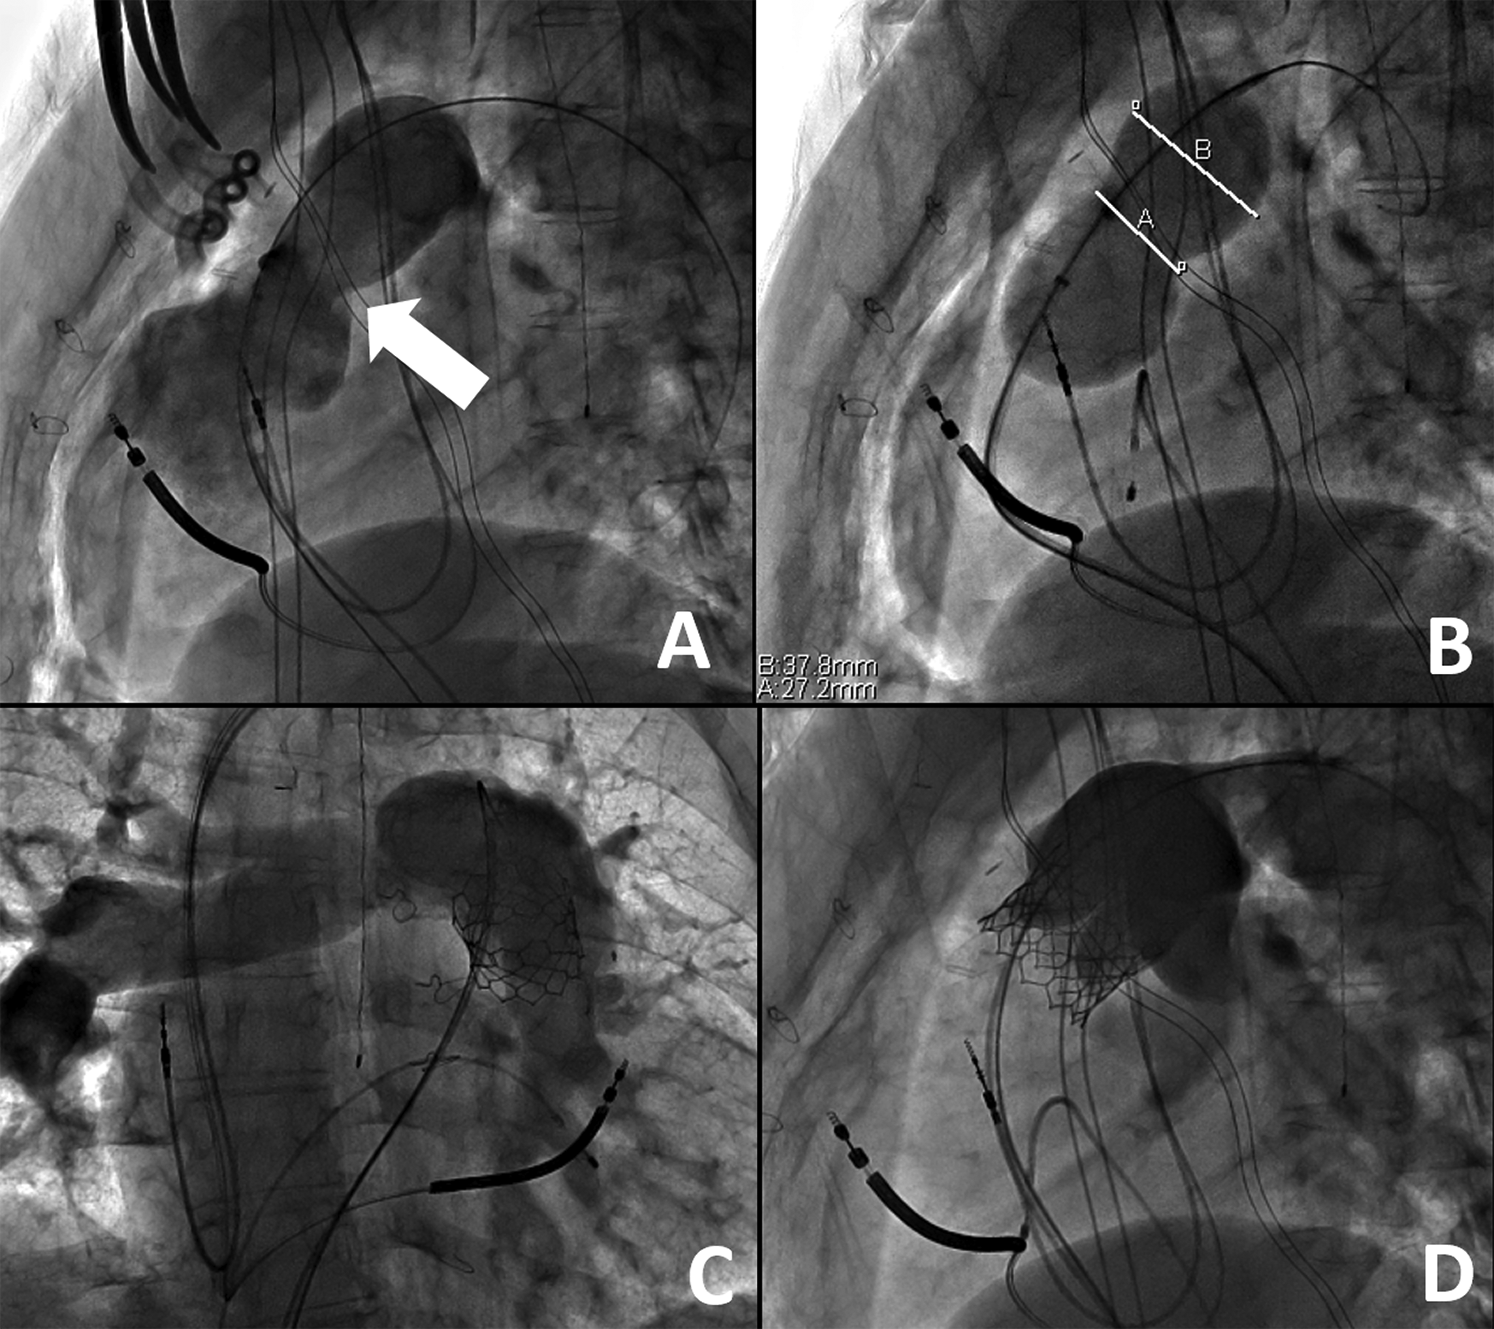

Hybrid PVR entailed off-pump RVOT-PA plication with subsequent transcatheter PVR occurring during the same procedure. All procedures were performed in a hybrid catheterization suite under general anesthesia. A femoral venous catheter was advanced to a distal PA branch. Full median sternotomy was then performed to expose the main PA, with minimal dissection of the heart and aorta. RVOT angiography was performed to obtain a roadmap of the anatomy with the open chest. An approximate measurement of the main PA was made to assist in determining the appropriate extent of plication (Fig. 1). Main PA/RVOT plication was performed with multiple pledgeted horizontal mattress sutures to provide an elongated, waist-like reduction of the selected landing zone. If there was calcification of a preexisting RVOT patch, a mattress suture, usually 4.0 Prolene (Ethicon, Somerville, NJ), was used to provide focal narrowing of the RVOT to approximately the required minimal diameter for the planned transcatheter device. Circumferential dissection of the main PA was not required. Following completion of mPA/RVOT plication, repeat RVOT angiography and balloon sizing was performed to re-assess the anatomy of the landing zone and ensure that a diameter suitable for a transcatheter valve was achieved (Fig. 2). If the post-plication diameter was still too large for the valve, then further plication was performed. If clinically indicated for the valve system (e.g., - Melody PVR, small conduits/RVOT < 24 mm, etc.), the main PA was pre-stented to create a landing zone for the valve construct and delivered via either femoral vein. In one patient, the delivery system could not be advanced from the femoral approach to the landing zone due to alteration in angle following RV plication. The valve was successfully delivered via a direct PA insertion. After deployment of a valve, the function of the valve was assessed by angiography and transthoracic echocardiography.

Figure 2: Right Ventricular Outflow Tract Rehabilitation via Hybrid Pulmonary Valve Replacement. A) Following surgical plication of the right ventricle, there is a new appearance to the right ventricular outflow tract on the lateral view with a new landing zone (white arrow). B) Upon balloon sizing, there are now measurements suitable for transcatheter pulmonary valve replacement as the narrowest portion measures about 27 mm. Following placement of a 29 mm Edwards Sapien transcatheter valve system (Edwards Lifesciences, Irvine, CA), there is a well seated valve in the anteroposterior (C) and lateral (D) views without any evidence for valve insufficiency